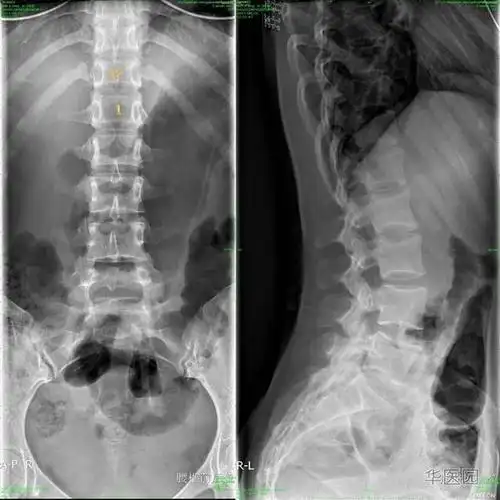

腰骶椎隐裂